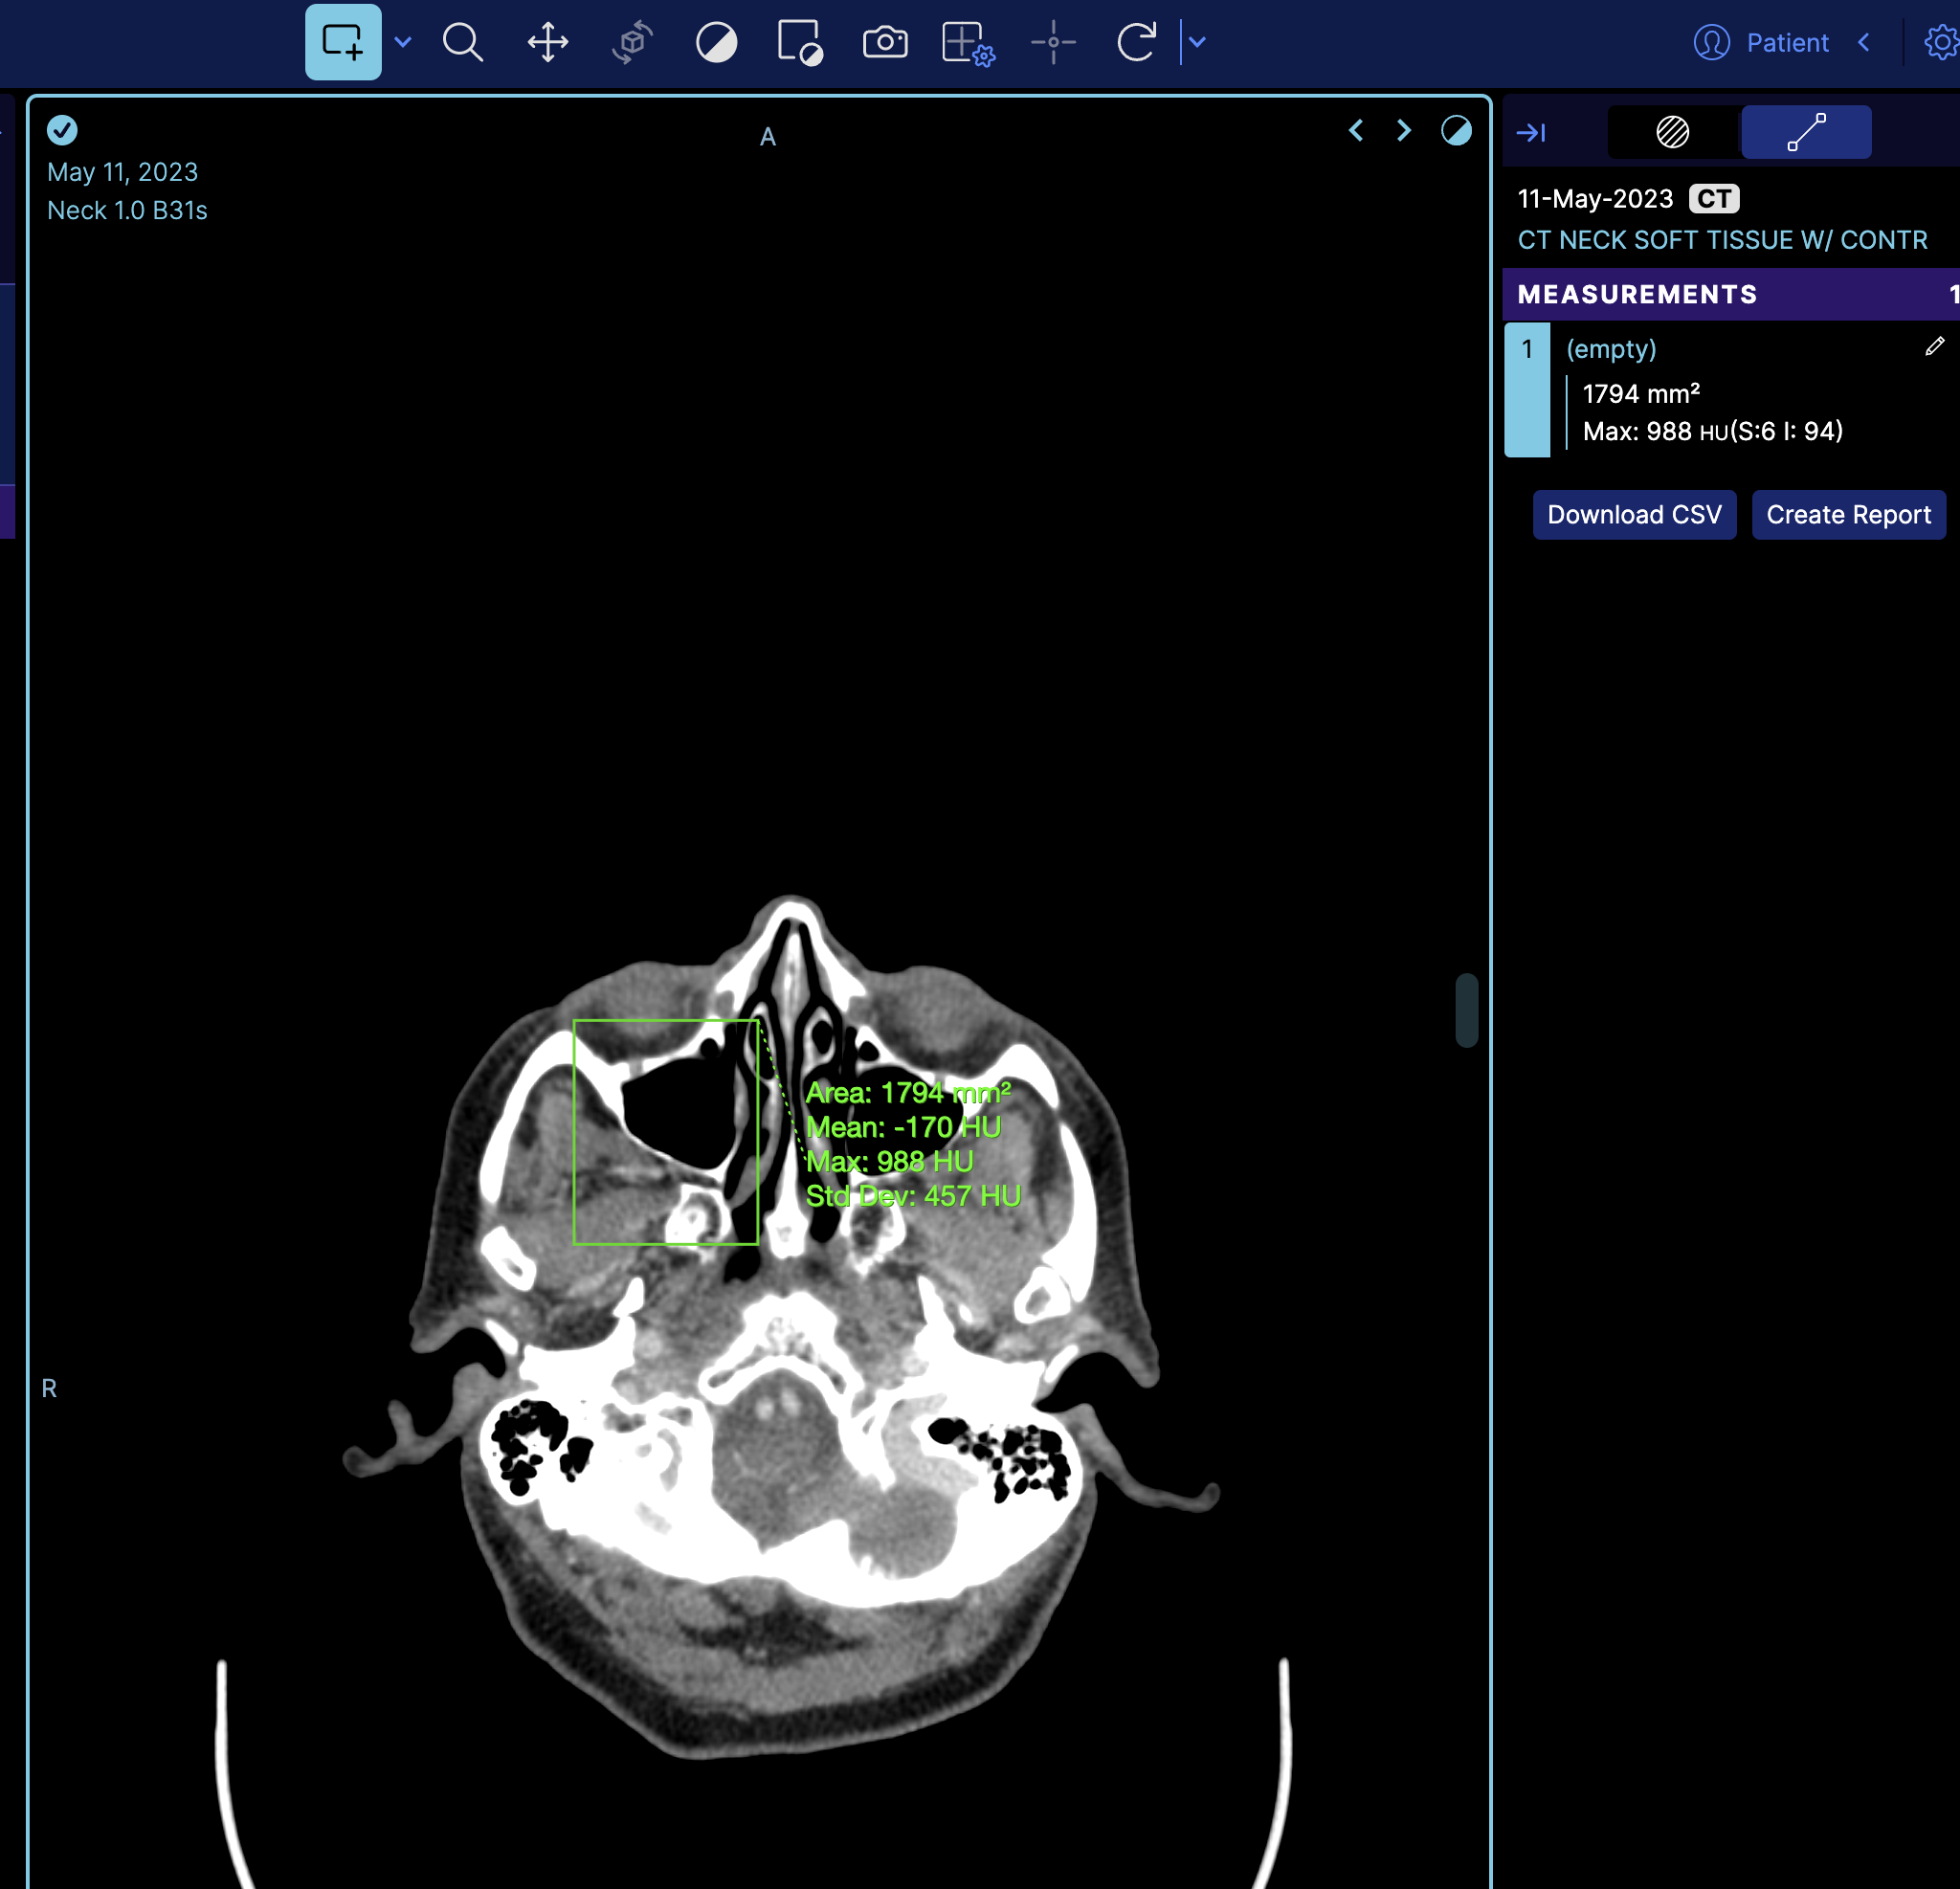

So if we look at the terminal and get the measurement service we can see there is one measurement

However, this is the mapped cornerstone measurement inside OHIF, and it has additional information such as geReport and source, which are internal details of OHIF Viewers that you don't need to worry about.

If you refresh the viewer, you'll see the measurement loaded on the image.

But if you notice it does not appear on the right panel, the reason is that the right panel is the tracking measurement panel. You can switch to a non-tracking measurement by changing

which then it will look like